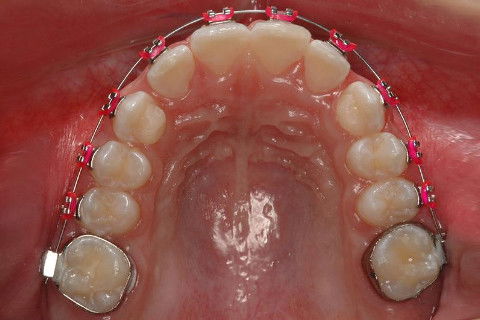

OCLUSAL SUP. INICIAL

INSTALAÇÃO APARELHO FIXO SUPERIOR E INFERIRO (ROTH)